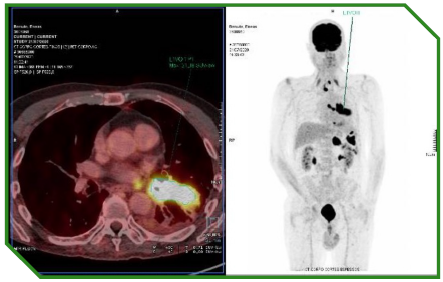

Paciente masculino de 78 anos com carcinoma espinocelular de laringe, tratado inicialmente com abordagem definitiva local, evoluindo posteriormente com recidiva local e progressão metastática pulmonar. Ao longo do curso da doença, foi submetido a múltiplas linhas terapêuticas, incluindo cirurgia, radioquimioterapia, quimioterapia sistêmica e imunoterapia isolada e em combinação, refletindo a complexidade do manejo longitudinal do R/M HNSCC.